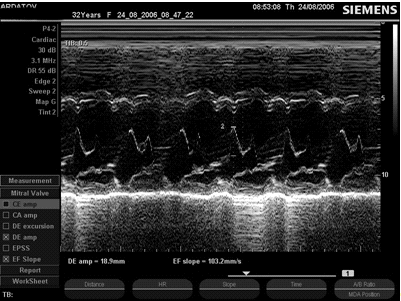

ЭхоКГ-критерии ПМК в М-режиме

1.       Позднесистолическое или голосистолическое выгибание одной или обеих створок по направлению к задней стенке левого предсердия более 3 мм.

2.       Диастолическое трепетание створок митрального клапана.

.        Увеличение диастолической экскурсии передней митральной створки.

.        Увеличение скорости раннего диастолического прикрытия передней митральной створки.

.        Увеличение систолической экскурсии межжелудочковой перегородки.

.        Увеличение систолической экскурсии задней стенки левого желудочка.

.        Дилатация аорты и увеличение ее систолической экскурсии.

Рис. 7. ПМК, М- и В-режим, длинная ось левого желудочка, парастернальный доступ.